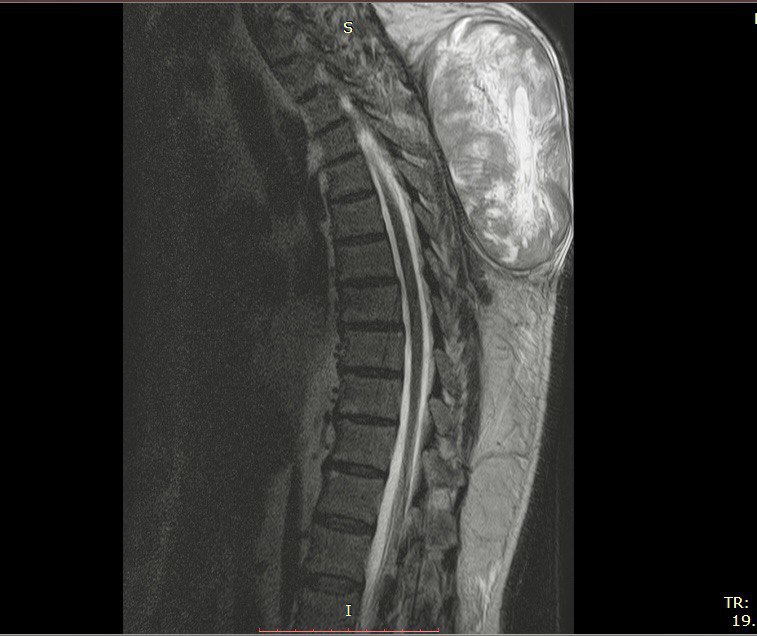

Перед проведением операции врачи провели комплексное обследование, включая магнитно-резонансную томографию и другие диагностические процедуры. Это позволило точно определить размер и расположение опухоли, а также возможные риски во время операции.

60-летний пациент, житель Тулы, поступил в нейрохирургическое отделение спинно-мозговой травмы (НХО СМТ) с серьезными симптомами, связанными с наличием опухоли. При обследовании врачи обнаружили, что опухоль значительно увеличивалась и могла вызвать опасные осложнения.